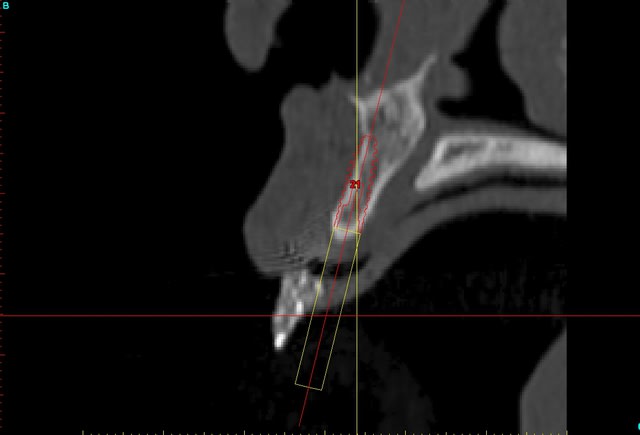

voilà, j'ai trouvé 5 mn...

le projet simplant est théorique, ça ne correspond pas à ce qui sera posé, c'était pour étude.